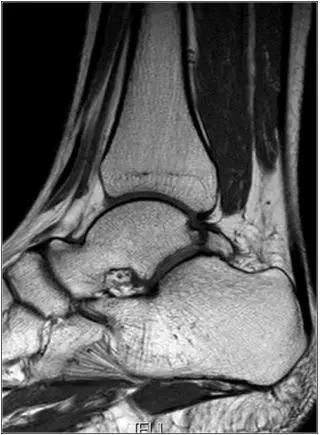

男,11岁,自述后踝下方疼痛,活动时为甚,并有一突起。

- MRI 检查示距后三角骨及周围软组织有水肿信号,距后三角骨和距骨之间正常的低信号纤维连接中断,出现液性信号。

3、MR表现:

- 三角籽骨或距骨后三角结构模糊和变形,T1WI信号降低, T2WI信号升高,

- 周围脂肪水肿,

- 踇趾长屈肌腱信号升高,见鞘膜积液,

- 胫骨后下跟骨上缘骨结构形态变化和信号异常,

- 三角籽骨和距骨退行性囊变。